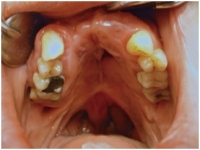

På klinikken fremstiller vi ganespalteprotester, også kaldet obturatorproteser.

De består af en ganeplade der dækker ganespalten mellem mundhulen og næsehulen. Ved at lukke ganespalten forhindres passage fra mundhulen til næsehulen, og det skaber en bedre lydresonans i udtalen.